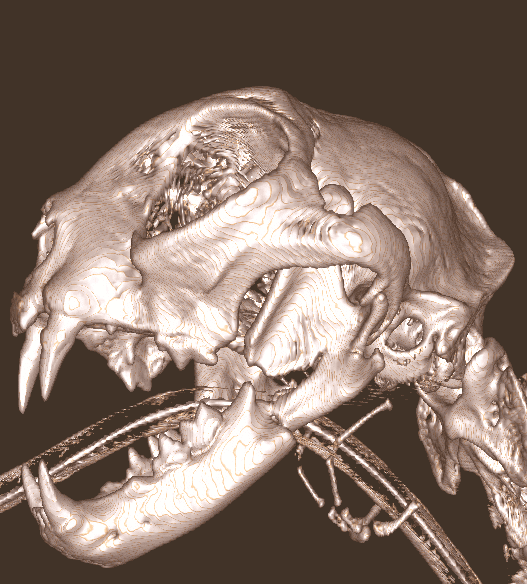

Repair of Maxillofacial Fracture

Pets can be involved in trauma that can cause fractures to their head, teeth, and jaw bones. Correctly repairing these fractures is extremely important for your pet to have normal function of their mouth. If a jaw fracture is allowed to heal in an abnormal position, your pet may have great difficulty chewing and can be in significant pain. Many fractures can be successfully treated with minimally invasive oral procedures, but more complicated cases may require bone plating techniques. The Center offers cone beam CT imaging which provides extremely detailed images of the bones of the head and skull. Advanced imaging with CBCT facilitates selection of the best surgical technique to get your pet back to eating and comfort as soon as possible.